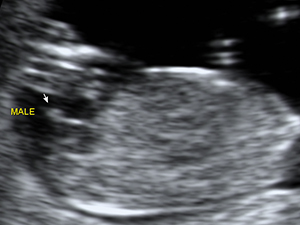

Male genital organ (arrow) at 18 weeks

Male genital organ (arrow) at 18 weeks Gender - Female